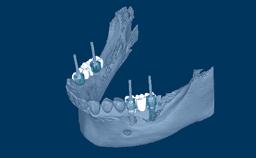

Complete dentures have a longstanding record for rehabilitation of edentulous jaws, but are frequently associated with problems of retention and stability. Patients with these issues may be referred for implant therapy often without first addressing problems of inadequate design and fit of the complete prostheses.

Improving the design and construction of the prostheses may alleviate problems of retention and stability without the need for implants. Therefore, the first step in the rehabilitation of edentulous arches is to establish whether or not the prostheses are adequate.

This module is a prerequisite to the Learning Module titled 'Complete Removable Overdentures: Implant Configuration and Retention'.